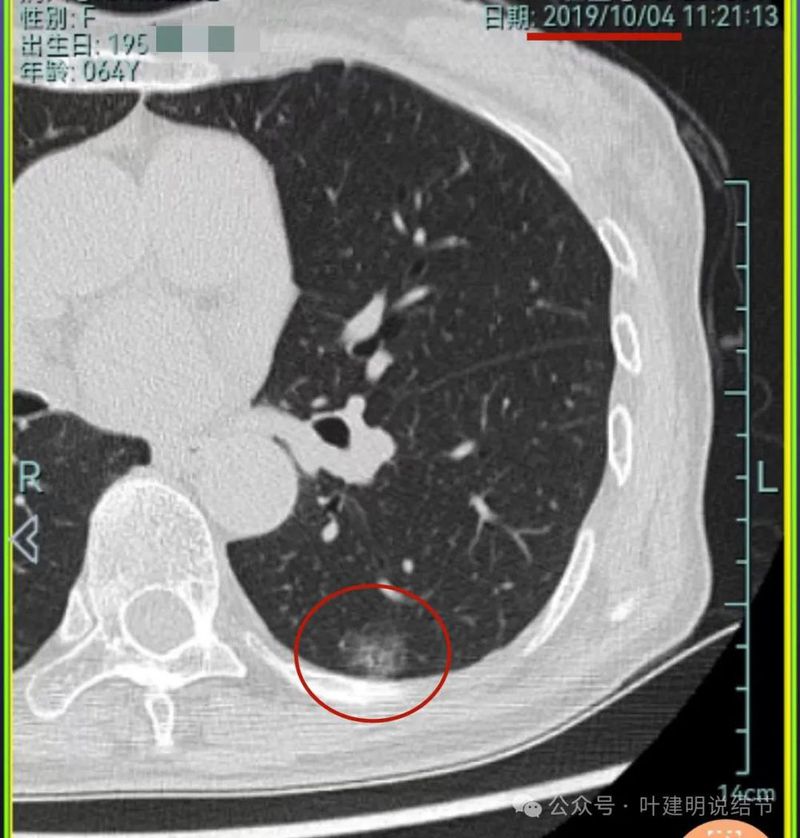

再看2023年8月的影像:

病灶1没什么进展。

病灶2与前相仿。

病灶3仍混合密度,说不上显著进展。

病灶4 仍是钙化的,大小也没有进展。

病灶5较前密度又有增高,贴着叶间裂,整体轮廓显得较之前清楚些,更符合恶性表现了,而且应该是浸润性腺癌。

病灶6与前相仿。